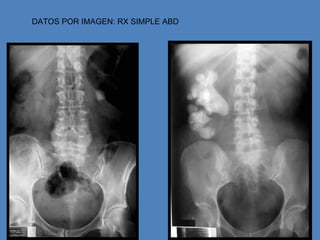

DATOS POR IMAGEN: RX SIMPLE ABD

RX ABDOMEN

Cálculos visibles en el 90% de los casos = radiopacos

10% radiotransparentes :::: ácido úrico %

sulfamidas

xantina

• Radiografía simplede abdomen. Presencia de cálculos radio-opacos • Una Pielografía o Urografía Intravenosa

DATOS POR IMAGEN:RX SIMPLE ABD

RX ABDOMEN Cálculos visiblesen el 90% de los casos = radiopacos 10% radiotransparentes :::: ácido úrico % sulfamidas xantina ECOGRAFÍA Detecta todos los cálculos incluidos los radiotransparentes Efectiva en riñón, uréter lumbar y cercanías de vejiga Ineficaz en trayecto ureteral no valorable (gas intestinal) Detecta hidronefrosis